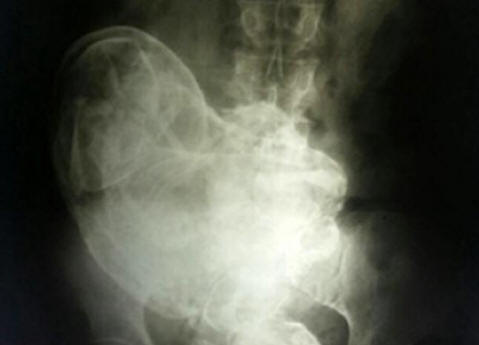

В утробата на 84-годишна бразилка открила вкаменено плод 44 години. Това се случи, когато поради непоносимо коремна болка жена се консултира с лекар, който я направи Рентгенова. На снимката те видяха вкаменен ембрион. Това явление получили в медицинска употреба името литопедион. Литопедион – вкаменен маточен плод, умрял в матката или корема кухина, която след това претърпя калцификация. Това е рядкост явление, което се проявява главно, когато плодът умира по време на извънматочна бременност. Тъй като няма естествено начин да се отървем от такъв плод, тялото го излага калцификати за предотвратяване на увреждането на плодовата тъкан тялото на носача. Лекарите, които прегледаха жената, стигнаха до заключението че плодът умря на 28-та седмица от бременността. не зависимо от операцията пациентът отказа да го премахне. Марокански случай Това явление е много рядко, така че обикновено са случаите на неговото появяване записани от историци. Този е описан през 2012 г. Жител на малко селце, разположено в близост до Казабланка, Мароко, майка на три деца Zahra Абуталиб за последно забременяла на 26-годишна възраст. Девет месеца от бременността плодът премина без усложнения. В болницата обаче тя стана свидетел смъртта на болничен съквартирант, млада майка, която почина на операционната маса в резултат на цезарово сечение. Неуспя да спаси детето си. Страхува се, че такава съдба може очаквайте я, впечатляващата Zahra , събираща неща, избяга от болници, решили да родят вкъщи. През следващите няколко дни тя страдаше страшно от родилни болки, колкото и дългоочаквани детето никога не е идвало на света. Скоро спря напълно се движат в утробата и жената реши, че бебето „заспива“. Захрадобре помни местния мит за „спящото бебе“. Уж ако не го роди, тогава той ще защитава честта на майка си през целия си живот. Следователно не особено притеснен за състоянието й, особено след като контракциите вече не се повтаря. Това продължи четиридесет и шест години, докато наскоро, вече на 75-годишна възраст, болката не се върна внезапно. Захрасе обърна към лекарите. Ехографски преглед в градска болница Рабат показа присъствието на чужда жена в корема тела, произходът на които лекарите не можаха да обяснят. това е проведе по-задълбочен преглед на тялото, според резултатите които експерти заключиха, че твърдата маса в тялото Захра не е нищо друго освен вкаменен плод, който е тялото на жената по чудо погрешно се сбърка с орган и следователно дълго време не възприема се като чуждо тяло. Операцията продължи четири часа. В крайна сметка екип от лекари, ръководен от д-р Тайби Куазани успя да извлече от тялото на жената плод с тегло малко повече от два килограми и с дължина 42 сантиметра. И така, след почти половин век, бебето на Захра най-накрая се роди

Снимка от открити източници Литопедионът се образува в тялото на жена в случай на смърт на плода, обикновено след извънматочна бременност, въпреки че има случаи на нейното образуване в матката. Тялото на майката възприема мъртвото дете като чуждо тяло, и в резултат на защитна реакция плода се мумифицира. първи подробно описание на такъв случай датира от 1582 г., когато е известно Френски лекар при аутопсия на 68-годишна жена откри вкаменен плод, останал в утробата на майката 40 години. Цялостна бременност Според медицинската статистика, “каменни деца” могат да останат вътре в човек, докато за дълго време. И 46 години в никакъв случай не е ограничението. И така, през януари 2009 г. през болница в китайския град Хуангиаотанг се превърна в 92-годишен местен жител Хуан Юйюн, който се оплака от много силна болка в стомаха. Каква беше изненадата на лекарите, когато разбраха това възрастна жена … бременна! Освен това, бременна за дълго време – 60 години! Нейната удивителна история, според The Sun, е започнала още през 1948г. Тогава лекарите казаха на Хуанг, че плодът е умрял и преди раждане в утробата си. За да го премахнете, беше необходима операция за която лекарите поискаха сума в местна валута, равна на 150 долара. Чувайки цените, Хуанг просто се обърна и си тръгна. „Това е навремето имаше много пари, казва жената, повече от всички членове на моето семейство спечелиха за няколко години. Следователно i Не съм направил нищо, решавайки да игнорирам медицинската диагноза. ” „Игнорирането“ продължи няколко десетилетия, докато починалият в утробата, детето не напомни отново. „Не можех да повярвам на моите на собствените му очи, когато откри, че в утробата е Yuijun дете ”, казва д-р Лю Ан Бин от болница Gwingsheng. – за 40-годишната ми практика като медицинско лице не е нищо повече Не съм виждал нещо странно или изненадващо. ” Акушерство и гинекологична болница Xu Xiang Ming добавя: „Обикновено мъртъв плод се разпада вътре. Но в случая се занимаваме рядко събитие. Все още не е ясно как г-жо Yuijun остана през цялото това време в добро здраве. “Още въпроси причинява най-дългата за днес в историята на медицината бременността на 93-годишната жителка на Лисабон Мария Романдес, която постъпил в болницата през 1996 г., оплаквайки се от силна болка в стомаха. Каква беше изненадата на лекарите, когато разбраха това възрастна жена е бременна с два мумифицирани плода 72 година! Баба си спомня, че през 1924 г. се разболяла, нея болна, тя наддаваше на тегло. В същото време се наблюдава спиране менструален цикъл. Жената осъзнала, че има някакъв проблем от женска страна, но тъй като не чувствах особено силни болки, Не ходих и на лекар. След известно време гадене мина, а Мария не се оплаква от здравето си до пролетта на 1996г година. След като установили причината за „болестта“, лекарите незабавно направи операция и отстрани две добре запазени изтръпнали близнаците. Експертите смятат, че са умрели от неуспех мощност. Липсата на хранене се превърна в причината за това тялото на Мария Романдес не ги хвърли навреме.